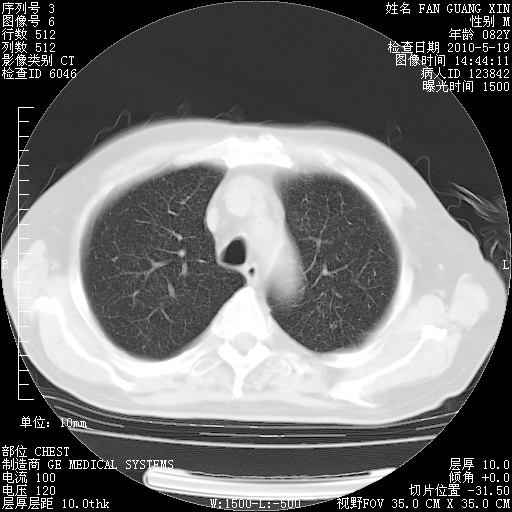

可改为口服强的松40-50mg/d治疗,若病情仍稳定,胸部阴影不再吸收可逐渐减量